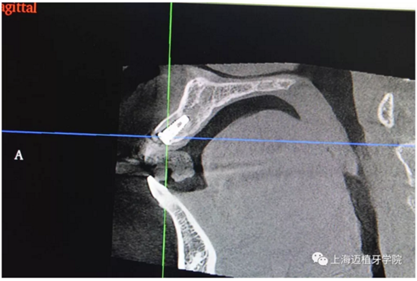

主訴:前門外傷牙根折要求修復(fù)?現(xiàn)病史:前門牙外傷,劈裂至根部,無法固定及其他修復(fù),要求種植?檢查:11牙冠2/3缺損,唇腭向劈裂,唇部紅腫。 CT示根折, 骨寬度9.47mm,距鼻底12.34mm,Ⅲ類骨。 口腔衛(wèi)生一般

植入植體DTS:4.1*10 15A042/0061